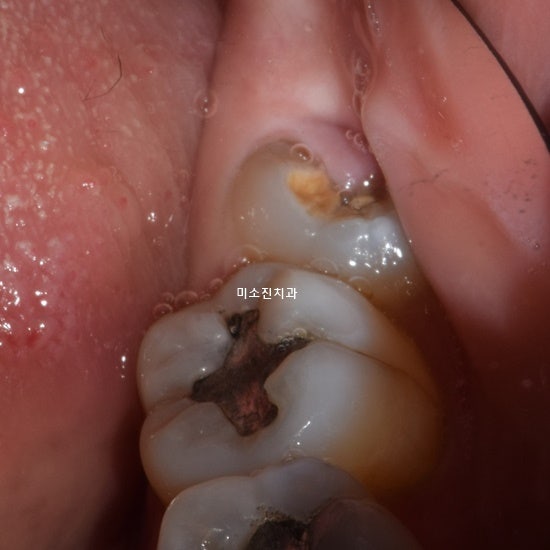

사랑니는 출생 후 어느 시점부터 잇몸 통증이 생기기 시작하지 않았나요? 정상적인 사랑니는 일반적으로 통증이 없지만 눕거나 비뚤어져 사랑니에 영향을 미치는 경우 잇몸 통증을 유발합니다. 입안 깊은 곳에 있기 때문에 치아가 음식에 닿지 못하고 음식을 꺼낼 수 없을 뿐만 아니라 염증과 충치가 생기기 쉽고 불완전한 잇몸으로 인해 잇몸과 다른 치아에 염증이 생기게 됩니다. 분화. , 충치와 같은 부작용을 유발합니다.

간혹 사랑니를 발치해야 하는지 고민하시는 분들이 계시는데, 사실 사랑니는 상황에 따라 발치가 필요하지 않은 경우도 있습니다. 사랑니는 가지런히 나고 잘 관리하면 큰 문제는 없으나 대부분의 사랑니는 좁은 공간에서 억지로 자라기 때문에 잇몸에 염증이 생기기 쉽고 관리가 어렵고 영향이 좋지 않습니다. 잇몸이 붓고 아프기 때문에 잇몸이 붓고 아프면 사랑니를 발치할 수 있습니다.우리는 당신이 할 것을 권장합니다

비교적 쉬운 일반 사랑니는 2D X-ray 검사만으로 발치를 할 수 있지만, 누수 매복 사랑니는 신경과의 관계상 3D CT를 이용하여 구강 구조를 진단하는 것이 가장 좋습니다. 잇몸과 뿌리의 상태, 방사선 사진으로는 볼 수 없는 인접치아의 거리와 각도, 발치가 어려운 경우에도 안전하게 할 수 있습니다. 알고 걷는 것이 중요합니다. )